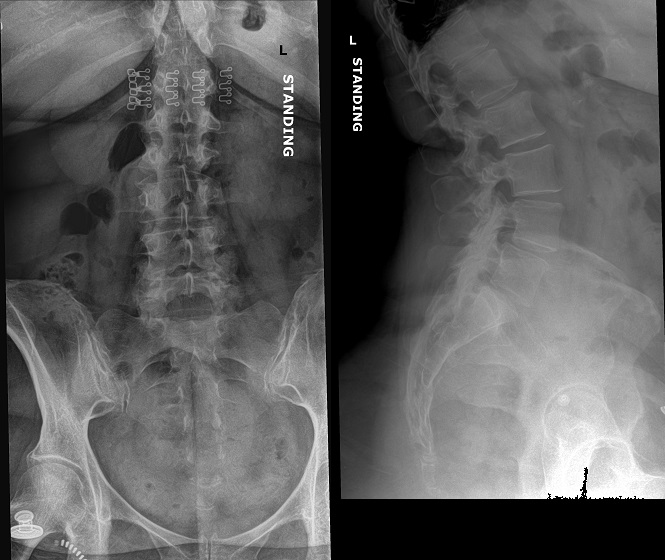

An 80 year old female presents to your office with a left ring finger deformity after a fall one week ago. She initially went to urgent care and xrays were unremarkable for a fracture (Figures 1 and 2). A photo of her left ring finger is shown in figure 3. On physical exam the left ring finger is in hyperextension at the PIP joint and flexion at the DIP joint. She able to flex her PIP joint with full motion. What is the best treatment option?